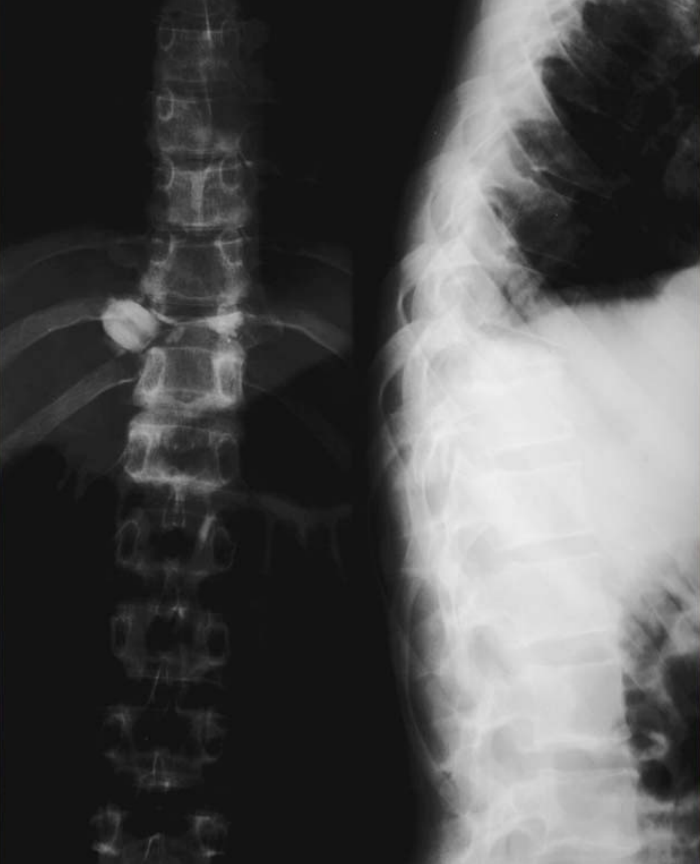

Figure4